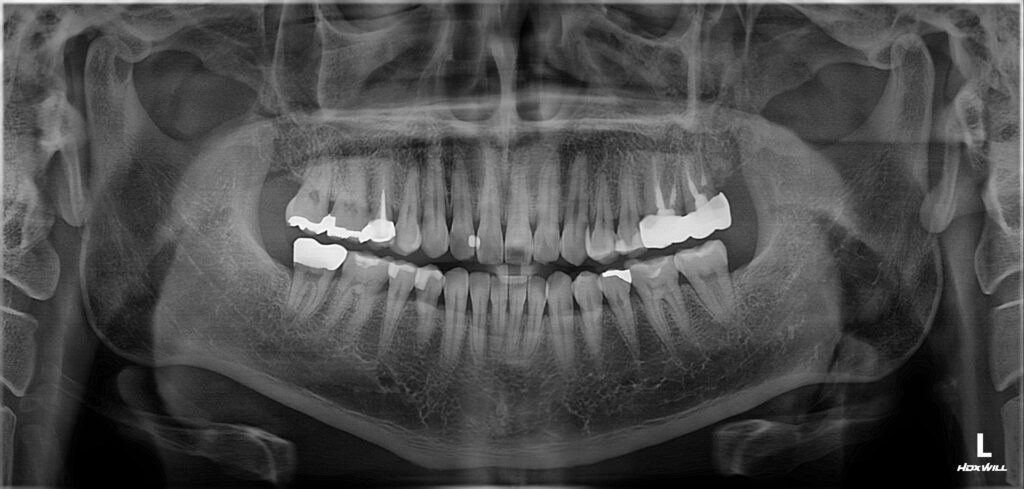

치아의 결손부를 충전하는 방식은 다양합니다.

인레이, 크라운 처럼 간접 수복물을 선택할 수 있고

레진, 아말감 처럼 직접수복을 선택할 수 도 있는데요.

간접 수복물은 기공을 해야하기 때문에

불필요한 치아 삭제가 동반되는 것을 피할 수 없어

레진 빌드업은 필요한 부분만 레진을 쌓아 올려

새로운 치아를 만들어주는 방법을 말합니다.